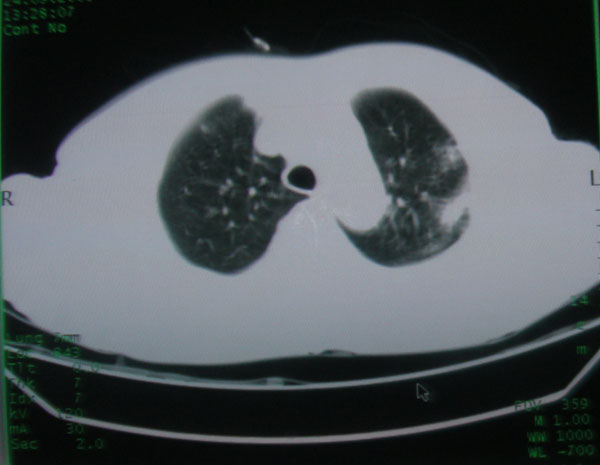

患者男性58岁因二周前起咳嗽,今天胸片示左上肺占位性病变行ct检查,无发热,无咯血痰.

左上肺感染性病变,结核伴空洞形成可能,左上肺膨胀不全

左肺上叶病灶,实变但见含气支气管、空洞但未见壁内结节及积液;

考虑:①感染性病变(包括特殊感染型肺tb)

②肿瘤性病变(考虑患者年龄比较大的关系/所以不排除)

初学者。。。左肺空洞性病变,并可见阻塞性肺不张改变,鉴于患者为老年男性,且临床症状仅有咳嗽,全身中毒症状不明显,所以我首先考虑为左肺癌性空洞并左侧肺门淋巴结转移伴左肺阻塞性肺不张。结核性空洞放于第二位考虑,可以进行相关实验室检查。希望能有病理结果,谢谢!!!!!

左肺上叶实变影,内见支气管充气征及空洞影,病人年龄较大,无发热及结核中毒症状,心影左移,未见纵隔淋巴结肿大;不知实验室检查结果如何?有否嗜酸细胞增多,有没有进行治疗?就目前资料首先考虑1.感染性病变,2.慢性嗜酸性肺炎?可结合实验室检查并短期治疗复查,肺癌不能排除。